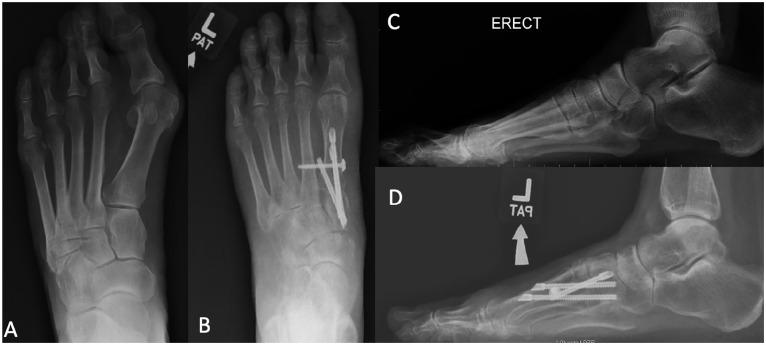

The Lapidus procedure corrects hallux valgus first ray deformity. First tarsometatarsal (TMT) fusion in patients with hallux valgus deformity using minimally invasive surgery (MIS) is a new technique, but comparative outcomes between MIS and open techniques have not been reported. This study compares the early radiographic results and complications of the MIS with the open procedure in a single-surgeon practice.

47 MIS patients were compared with 44 open patients. Radiographic measures compared preoperatively and postoperatively were the intermetatarsal angle (IMA), hallux valgus angle (HVA), foot width (FW), distal metatarsal articular angle (DMAA), sesamoid station (SS), metatarsus adductus angle (MAA), first metatarsal to second metatarsal length, and elevation of the first metatarsal. Early complications were recorded, as well as repeat surgeries.

The mean follow-up was 82 (range, 31-182) months for the open group and 29 (range, 14-47) months for the MIS group. In both techniques, postoperative measures (IMA, HVA, DMAA, FW, and sesamoid station) were significantly improved from preoperative measures. When comparing postoperative measures between both groups, the IMA was significantly lower in the open group (4.8 ± 3.6 degrees vs 6.4 ± 3.2 degrees, < .05). Differential between pre- and postoperative measures for both techniques were compared, and the open group was associated with more correction than the MIS group for IMA (12.4 ± 5.3 degrees vs 9.4 ± 4.4 degrees, = .004) and HVA (25.5 ± 8.3 degrees vs 20 ± 9.9 degrees, = .005). Wound complication and nonunion rates trended higher in the open group (4 vs 0) ( = .051).

Both techniques resulted in good to excellent correction. However, the open technique was associated with lower postoperative IMA values and more correction power for IMA and HVA, than the MIS.